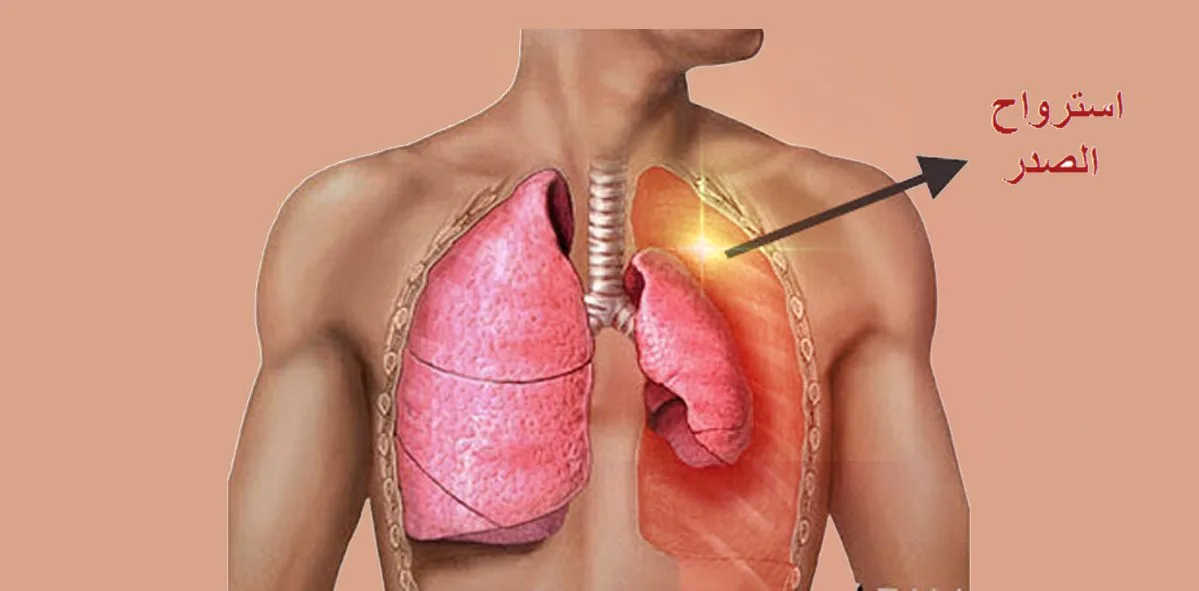

ما هو إسترواح الصدر؟

إسترواح الصدر (Pneumothorax) هو حالة طبية تحدث عندما يتجمع الهواء في الفراغ بين الرئة وجدار الصدر. هذا التجمع يسبب ضغطاً على الرئة مما يؤدي إلى انكماشها أو انهيارها الجزئي أو الكامل. يمكن أن تحدث هذه الحالة بشكل مفاجئ وتعتبر حالة طبية طارئة تتطلب العلاج الفوري.